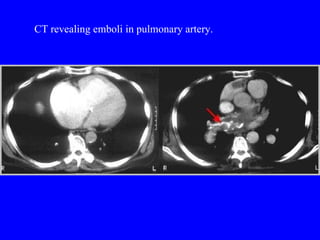

Spiral CT Scan Identifies proximal PE (which are the ones usually hemodynamically important) Not as accurate with peripheral PE

CT revealing emboli in pulmonary artery.

Spiral CT ScanIdentifies proximal PE (which are the ones usually hemodynamically important) Not as accurate with peripheral PE

CT revealing emboliin pulmonary artery.